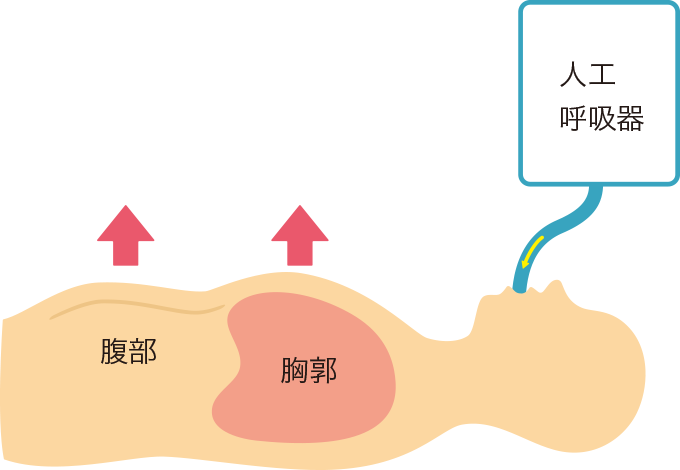

気管チューブの誤抜去が予想される場合、呼吸状態の観察を行います。人工呼吸器の換気により胸郭が挙上するか(図1)、左右差がないか、聴診では呼吸音の異常音や左右差がないか観察します。

図1換気時の胸郭挙上